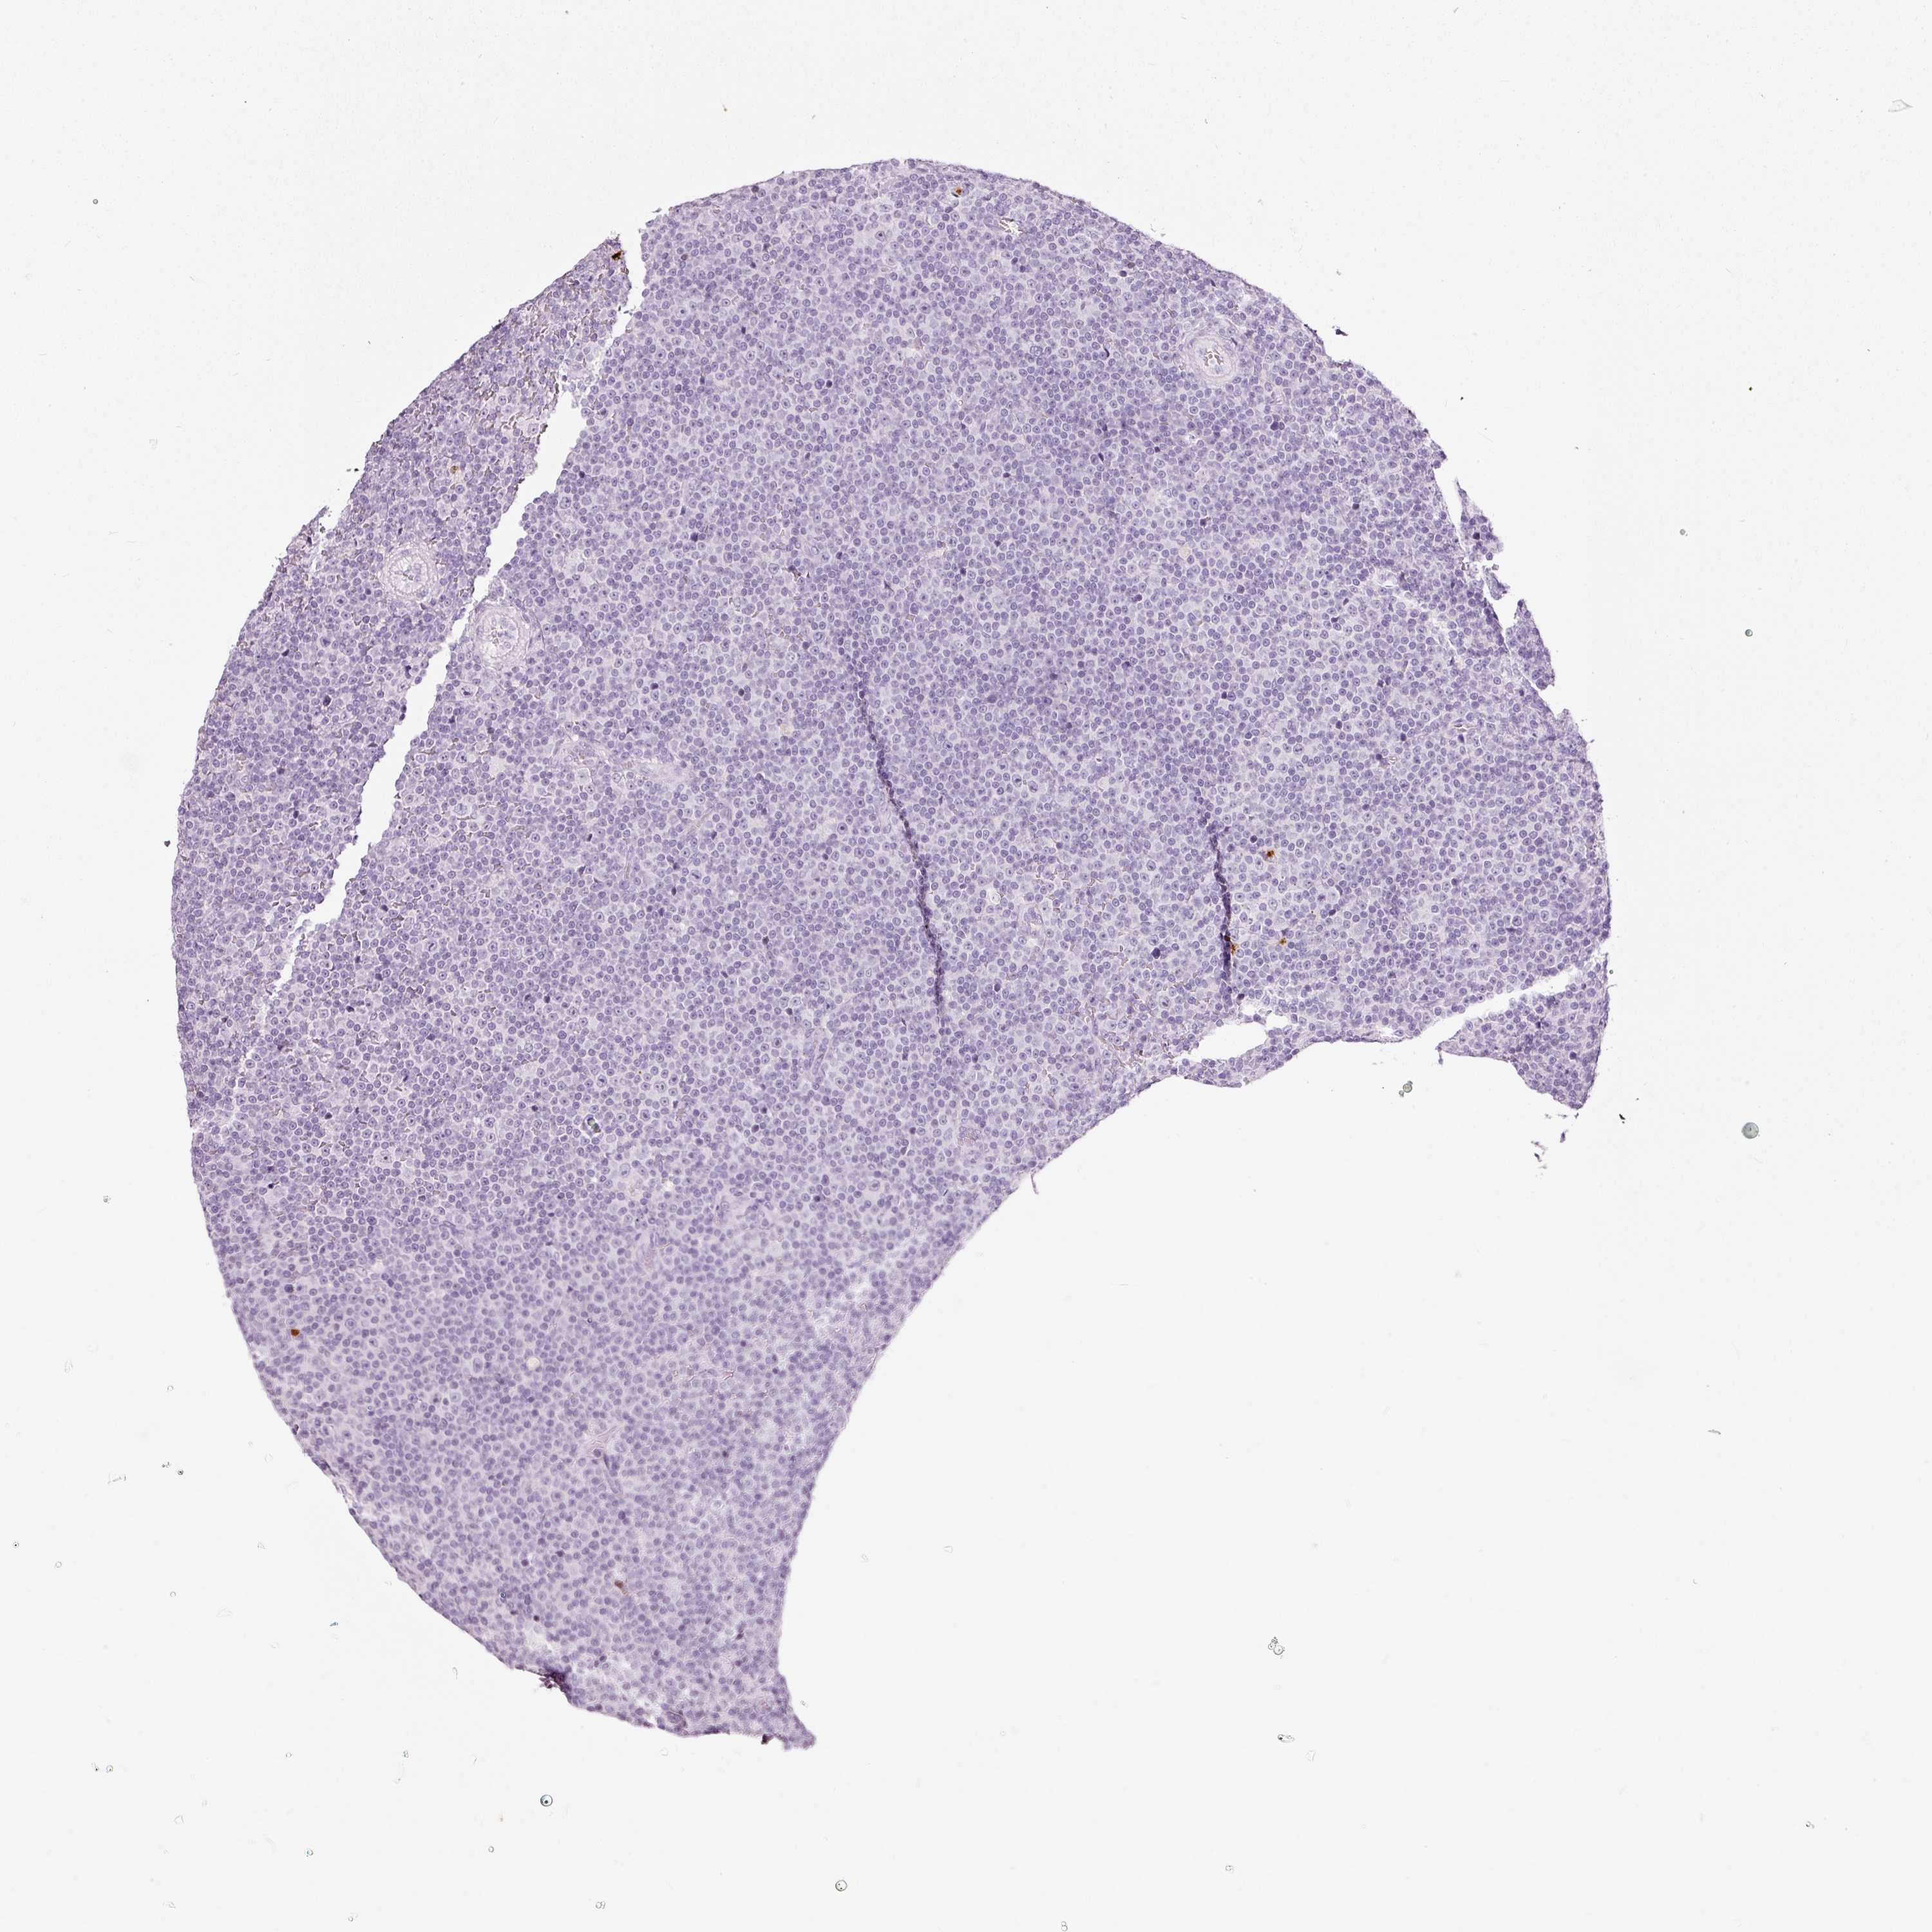

LYMPHOMA - Protein expressioni

A mouse-over function shows sample information and annotation data. Click on an image to view it in a full screen mode. Samples can be filtered based on level of antibody staining by selecting one or several of the following categories: high, medium, low and not detected. The assay and annotation is described here.

Antibody stainingi

Antibody staining in the annotated cell types in the current human tissue is reported as not detected, low, medium, or high, based on conventional immunohistochemistry profiling in selected tissues. This score is based on the combination of the staining intensity and fraction of stained cells.

Each image is clickable and will lead to virtual microscopy that enables deeper exploration of all samples and also displays staining intensity scores, fraction scores and subcellular localization as well as patient and tissue information for each sample.

Antibody HPA051467

Antibody CAB025133

Staining

High

Medium

Low

Not detected

Intensity

Strong

Moderate

Weak

Negative

Quantity

>75%

75%-25%

<25%

None

Location

Nuclear

Cytoplasmic/membranous

Cytoplasmic/membranous,nuclear

Hodgkin's disease, NOS

Malignant lymphoma, non-Hodgkin's type, High grade

Malignant lymphoma, non-Hodgkin's type, Low grade